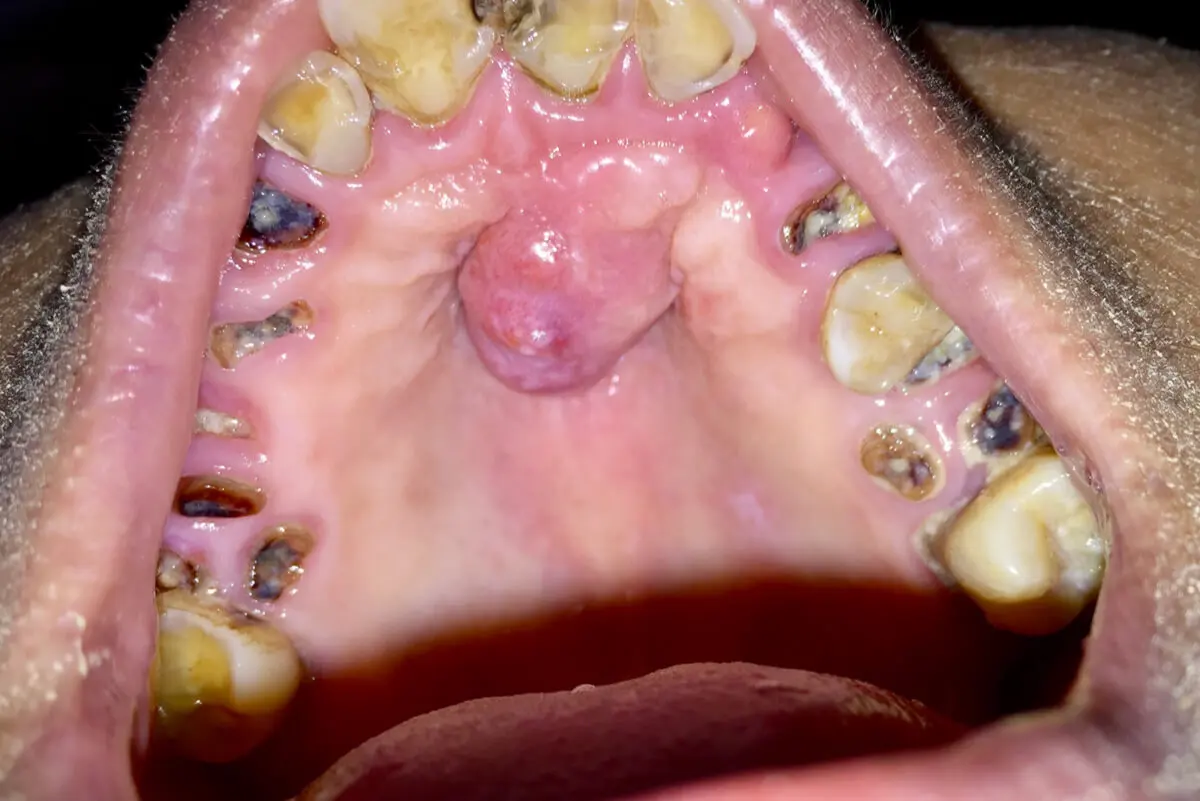

Granuloma piógeno

Es un bulto de paladar común en las mujeres embarazadas. Esta protuberancia tiene color rosado, es blando y si se irrita puede sangrar.

La ubicación más usual es en el centro del paladar. Aunque sea una alteración benigna, resulta molesta para el paciente, por lo que su tratamiento es la extirpación con una simple cirugía.